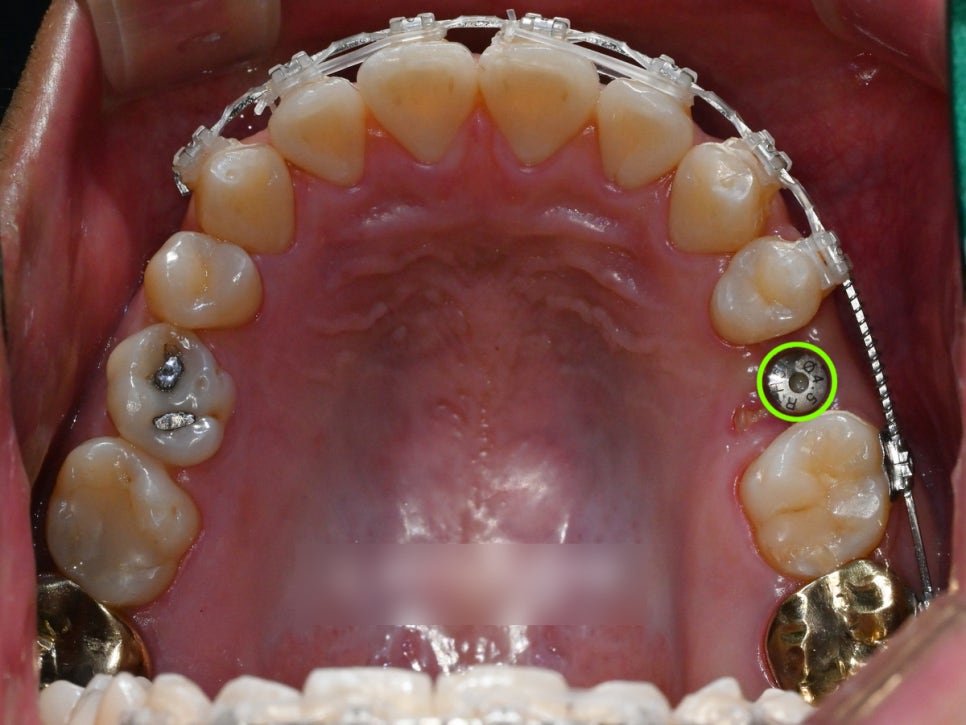

내원 당시 사진

당시, 위쪽 어금니 하나를

일찍 상실하여 임플란트 식립 예정인

상황이라는 점입니다.

그러나 이 상태가 꽤 오랜기간

방치가 되었는지 앞 어금니가 이동되면서

발치 공간이 줄어든 상태였습니다.

꼭 치료가 필요한 치아들에만 브라켓을 부착하여

불편함을 최소로 하고 배열하던 모습입니다.

중간에 엑스레이 촬영으로

치아들의 반응을 살펴주며

안전하게 배열했습니다.

크게 문제가 되는

부분은 없습니다.